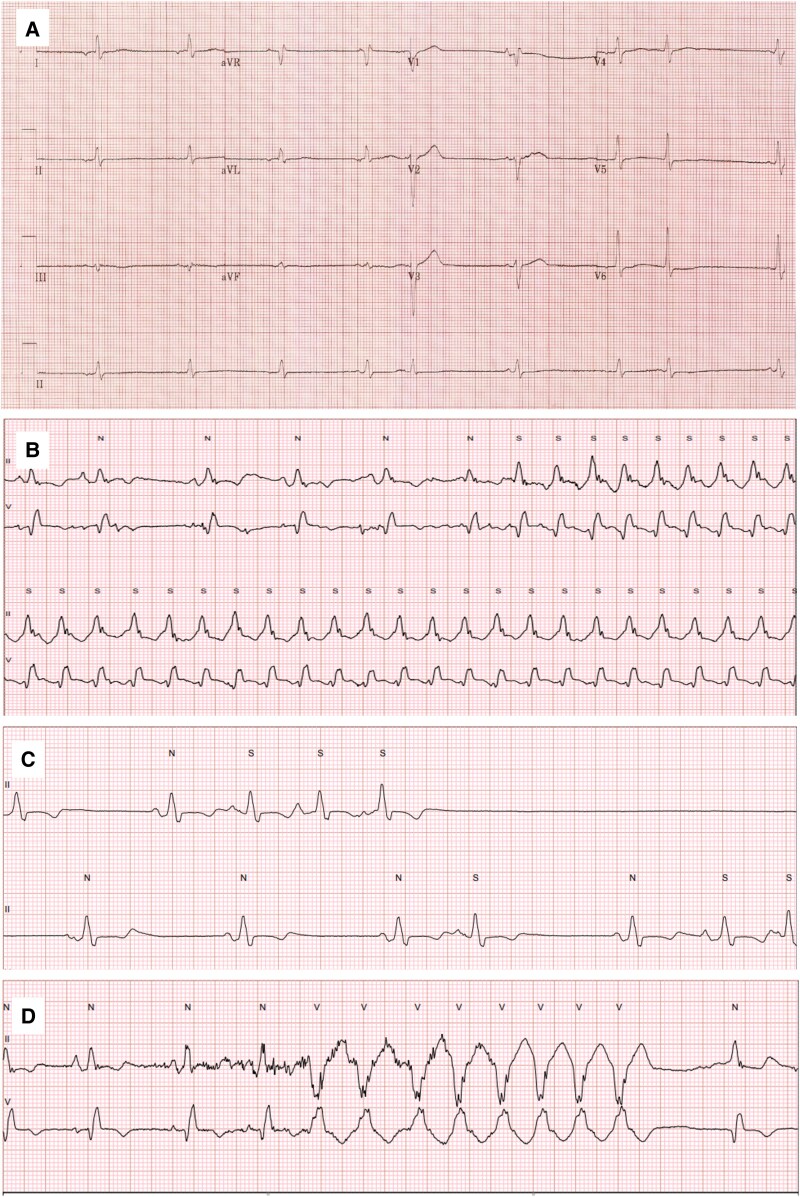

Case summary: A 56-year-old female with a longstanding history of systemic lupus erythematosus presented with progressive dyspnoea, fatigue, and fluid overload. Initial investigation revealed LVH with restrictive physiology, elevated cardiac biomarkers, and non-specific findings on echocardiography suggestive of an infiltrative cardiomyopathy. The diagnosis remained uncertain until an endomyocardial biopsy (EMB) confirmed HCQ-CM, characterized by the presence of curvilinear inclusion bodies. Following cessation of HCQ, there was a significant clinical improvement, with the patient achieving NYHA class I status at 6 months follow-up.